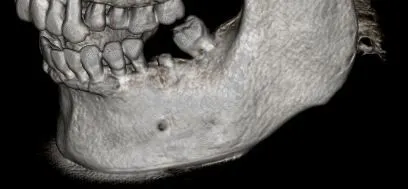

Cone Bean Computer Assembled Tomography

Our office uses the most advanced technology to treat our patients in the most effective way. We use the award-winning i-CAT 3D FLX Cone Beam Computer Assembled Tomography (CBCT) imagining system to acquire the most diagnostic image with less radiation than the average panoramic or traditional x-ray. The dose from this imaging system is 80-95% less than a medical Computed Tomography. With an extremely short scan, typically within five seconds, we can obtain enough data for a comprehensive diagnosis.

The type of radiation produced by the i-CAT is no different than that produced by any other x-ray machine. But with less radiation, one i-CAT scan can replace all of traditional images like panoramic, a lateral cephalogram (head film) and various periapical x-rays in just one click.

i-CAT 3D imaging provides exceedingly beneficial information about the following:

• Less radiation

• More details

• 3D image system

• Precise location of impacted teeth

• Precise measurement of implant placement

• Bone loss visualization

• Medical findings